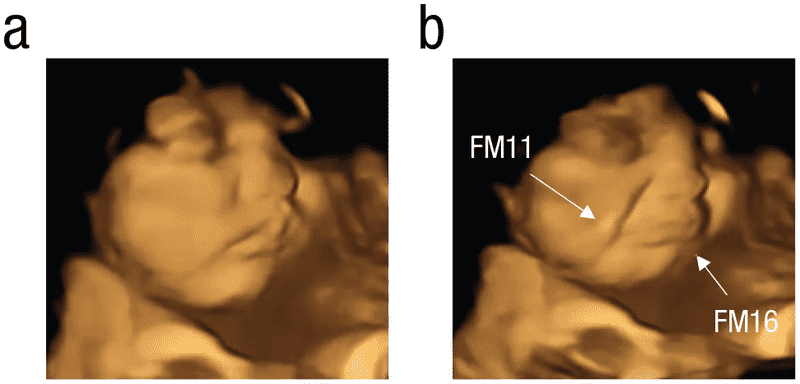

正如已经指出,胎儿开始妊娠14周后发展的味蕾。因此,在研究研究中,大约100名母亲在怀孕最后三个月了。形成了共三组,包括母亲使用超声波没有消费任何形式的食物。第二和第三组包含那些孕妇食用甘蓝或胡萝卜粉,太,大约20分钟前超声波。结果是迷人的。你可以看到在下面的图片中,胎儿在第二或第三组开始回应他们的母亲的味道通过面部表情。它是可爱的,不是吗?

加上这一点,研究人员继续为约25分钟超声波的过程,这样他们可以有效地、准确地扫描所有的面部表情和动作。正如你所看到的图片,胎儿暴露于甘蓝演示了一个哭脸,而胎儿母亲食用胡萝卜显示响应的形式“笑的脸。“这是难以置信的,但科学家仍模糊这迷人的现象背后的原因。